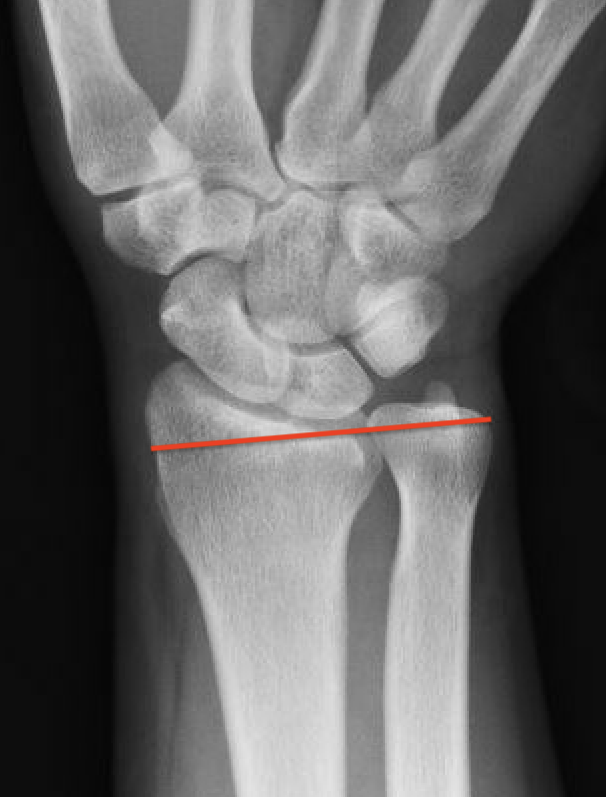

| Stage IIIB | Stage IV |

|---|---|

|

Collapse / fragmentation Scaphoid flexed / Capitate migrates proximally |

Pancarpal osteoarthritis |

![]() |